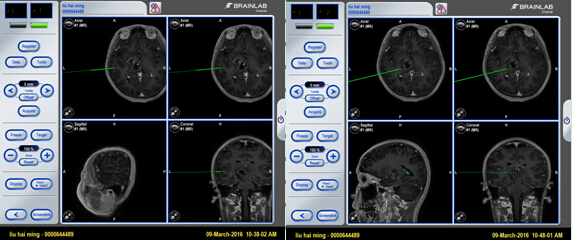

图1 术前MRI片

图3 术中神经导航精准定位肿瘤